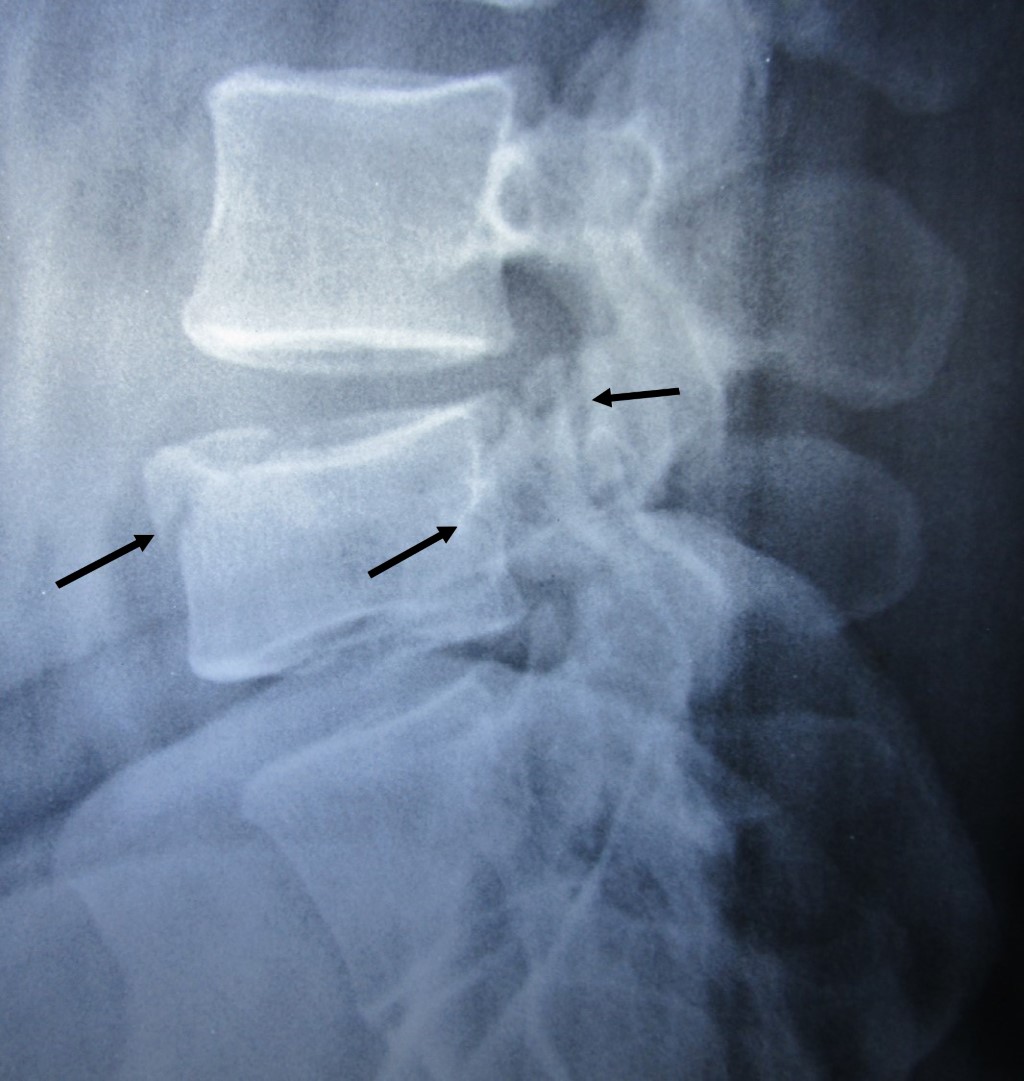

Chance´s fracture

Figure 1